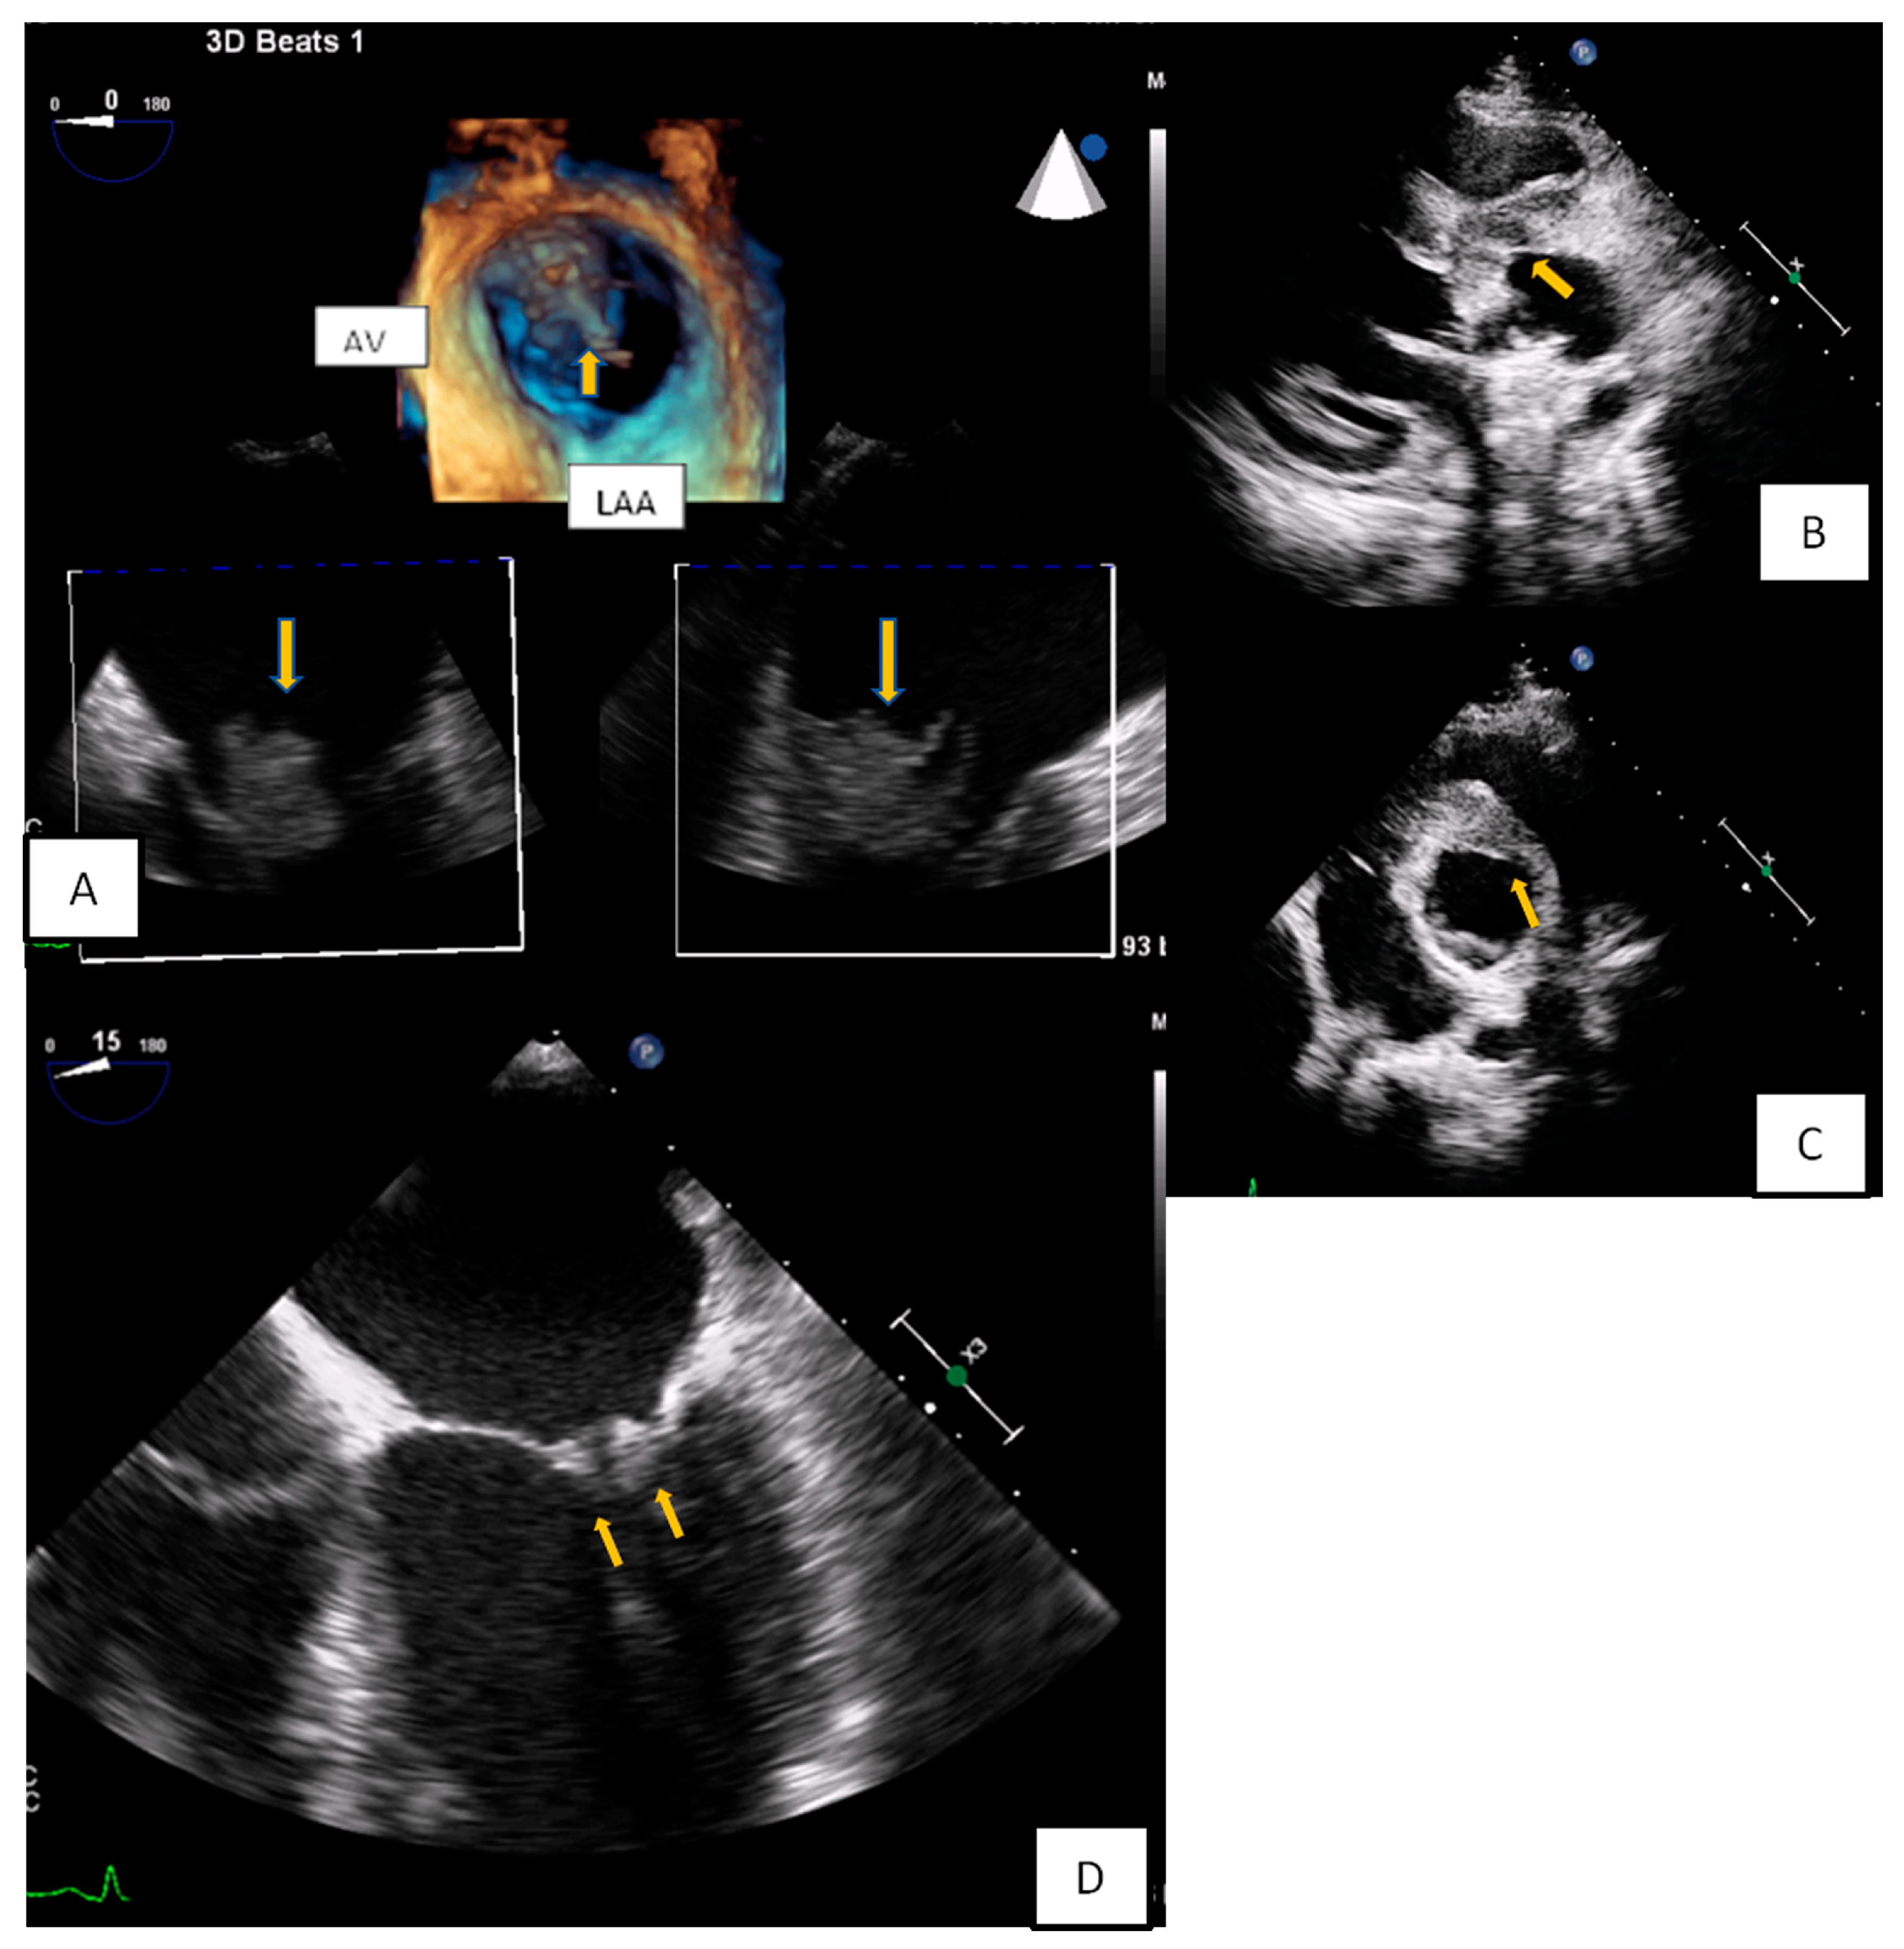

3.2. Transesophageal Echocardiography

- Zaragosa-Macias, E.; Chen, M.A.; Gill, E.A. Real time three-dimensional echocardiography evaluation of intracardiac masses. Echocardiography 2012, 29, 207–219. [Google Scholar] [CrossRef] [PubMed]

- Aggeli, C.; Poulidakis, E.; Felekos, I.; Aggeli, A.; Stefanadis, C. An octopus-like myxoma depicted by real-time 3D transesophageal echocardiography. Hell. J. Cardiol. 2012, 53, 470–471. [Google Scholar]